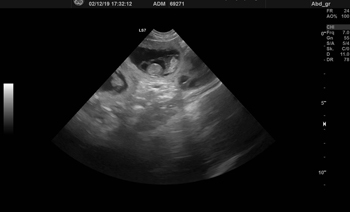

03.12.2019 Foundry´s A-Wurf - Full House Der gestrige Ultraschall bei Ylvi zeigte blitzfix sieben kleine Springerchen. Und wo sieben sind, können sich auch noch ein paar verstecken. ;-) Der Dezember mit seinen vielen Aktivitäten wird jetzt hoffentlich auch blitzfix vergehen. Anfang Januar gibt es dann endlich wieder Welpenquietschen im Haus.